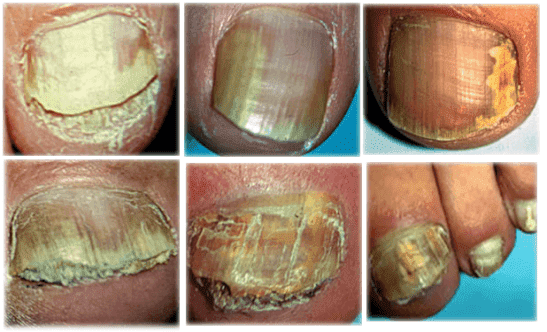

Ein Spezialist der Dermatologischen Klinik München meint: "Nagelpilz infiziert das Blut und verursacht Nekrose. Es gibt eine Lösung, aber die ist nicht für jeden geeignet".

Hier sind einige Auszüge aus der Pressekonferenz von Sarah Lohmann - Spezialistin in der Dermatologischen Klinik München. "Nagelpilze dringen in den Blutkreislauf und in die inneren Organe ein, wo sie Blutvergiftungen verursachen und den Körper zerstören. In Deutschland haben wir eine der höchsten Sterblichkeitsraten durch Nagelpilze weltweit. Jede infizierte Person stirbt innerhalb von 10 bis 14 Jahren".

Wissen Sie, wie viele Menschen im Jahr durch eine Pilzinfektion ums Leben kamen? Insgesamt starben im Raum München im vergangenen Jahr 55.000 Menschen. 31.000 davon hatten einen Fußpilz. Das entspricht mehr als der Hälfte aller Gestorbenen. Nagelpilze beeinträchtigen nicht nur unsere Zehennägel, sondern dringen in den Blutkreislauf ein und verbreiten sich so über den Fuß in den gesamten Körper. Der Pilz zerstört unseren Körper von innen heraus und sorgt bei allen Organen für Stress. Die kleinen Sporen heften sich an die inneren Organe an und vermehren sich, wodurch Schäden entstehen. So sind auch innere Organe von der Pilzinfektion betroffen. Das bedeutet, dass der Körper von innen heraus "verfault". Im Laufe der Zeit versagt das Herz, ein Blutgefäß im Gehirn kann explodieren oder es kann zu Leberkrebs kommen. Auch ein Nierenversagen ist möglich. Jeder, der an Nagelpilzen leidet, hat dieses Risiko. Das Immunsystem wird durch häufige Erkältungen geschwächt und der Stress tut sein Übriges, was zum plötzlichen Tod führen kann.

Aus diesem Grund sehe ich Nagelpilze als eine extrem gefährliche Krankheit an, die bundesweit für eine Vielzahl der Tode verantwortlich ist. Wir hören oft von Krebs und Tumoren, doch letztendlich betrifft das nur 3 bis 4 Prozent aller Menschen, wohingegen Nagelpilze bei 50% aller Menschen im Alter von 40 bis 45 Jahren vorhanden sind.

Die äußeren Symptome des Pilzes lassen sich recht gut behandeln, jedoch wird dadurch das tödliche Risiko einer Infektion nicht gemindert. Der Tod kann nach wie vor plötzlich auftreten.